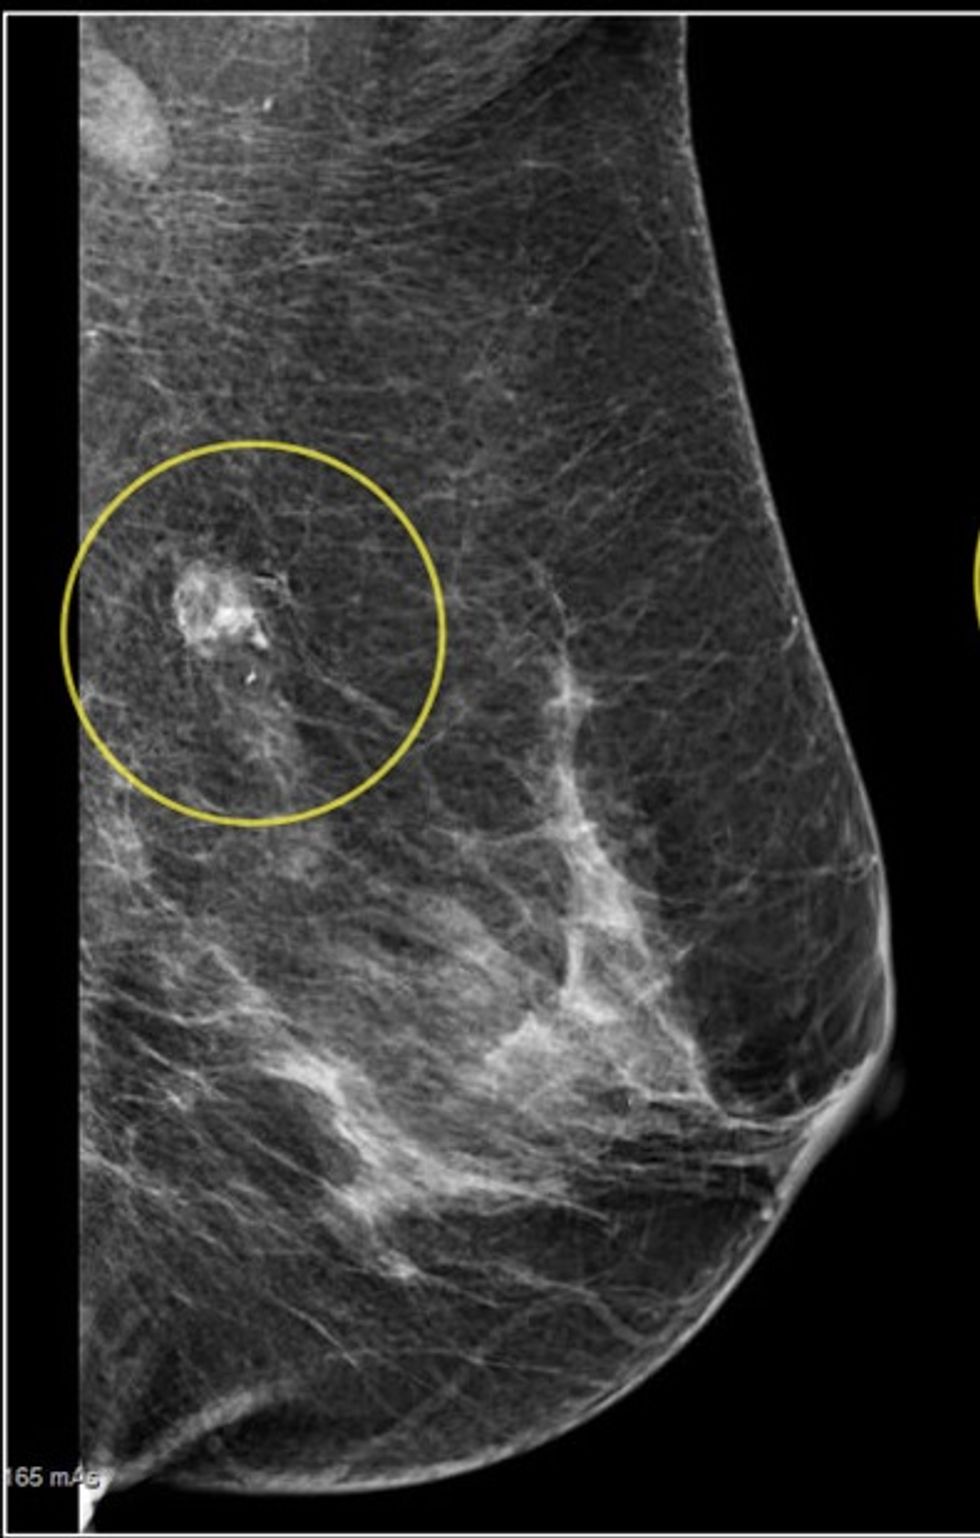

Spiculated Density:

This little bugger can really have you in the corner chewing your nails off. This was one of the findings on my mammogram last year. On a follow-up mammogram the darn thing performed a full disappearing act, not that I'm complaining. But... spiculated... that doesn't even sound like it belongs in my body and where in the world did it go? (I'm hearing Where in the World is Carmen San Diego now) .

So now that you have all of these scary sounding words in your result letter, what does it mean? This is a helpful chart to help untangle your jangled nerves.

Malignant or Benign?